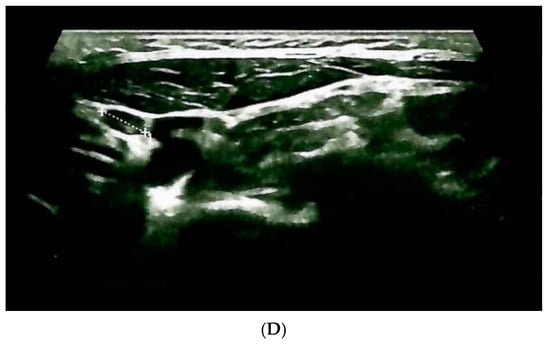

| Confirmation of the endocrine tumor/cancer | Yes (+2/10 cervical lymph nodes invasion) | Yes (bilateral) | Yes (left inferior parathyroid tumor) |

| Age at diagnosis | 31 years (+ RET testing at 31 years) | ||

| Hormonal assays before surgery | Calcitonin = 304 ng/mL (normal: 1–4.8) | Plasma metanephrines = 300 pg/mL (normal: 0–90) Plasma normetanephrines = 400 pg/mL (normal: 20–200) | PTH = 122 pg/mL (normal: 15–65) Total serum calcium = 11.4 mg/dL |

| Surgery | Yes (synchronous total thyroidectomy, neck lymph nodes dissection and selective removal of a single parathyroid tumor) | Yes (synchronous bilateral adrenalectomy) | Yes |

| Age at the moment of surgery | 31 years | ||

| Confirmation of the endocrine tumor/cancer | Yes (no lymph nodes invasion) | Yes (bilateral) | No |

| Age at diagnosis | 30 years (+RET testing at 30 years) | 32 years (left adrenal), respectively, 38 years (right adrenal) | No |

| Hormonal assays before surgery | Calcitonin = 74 ng/mL (normal: 1–4.8) | Plasma metanephrines = 148 pg/mL (normal: 0–90) Plasma normetanephrines = 78 pg/mL (normal: 20–200) | No |

| Surgery | Yes (total thyroidectomy + neck lymph nodes dissection) | Yes (asynchronous bilateral laparoscopic adrenalectomy) | No |

| Age at the moment of surgery | 30 | 32, respectively, 38 years | No |